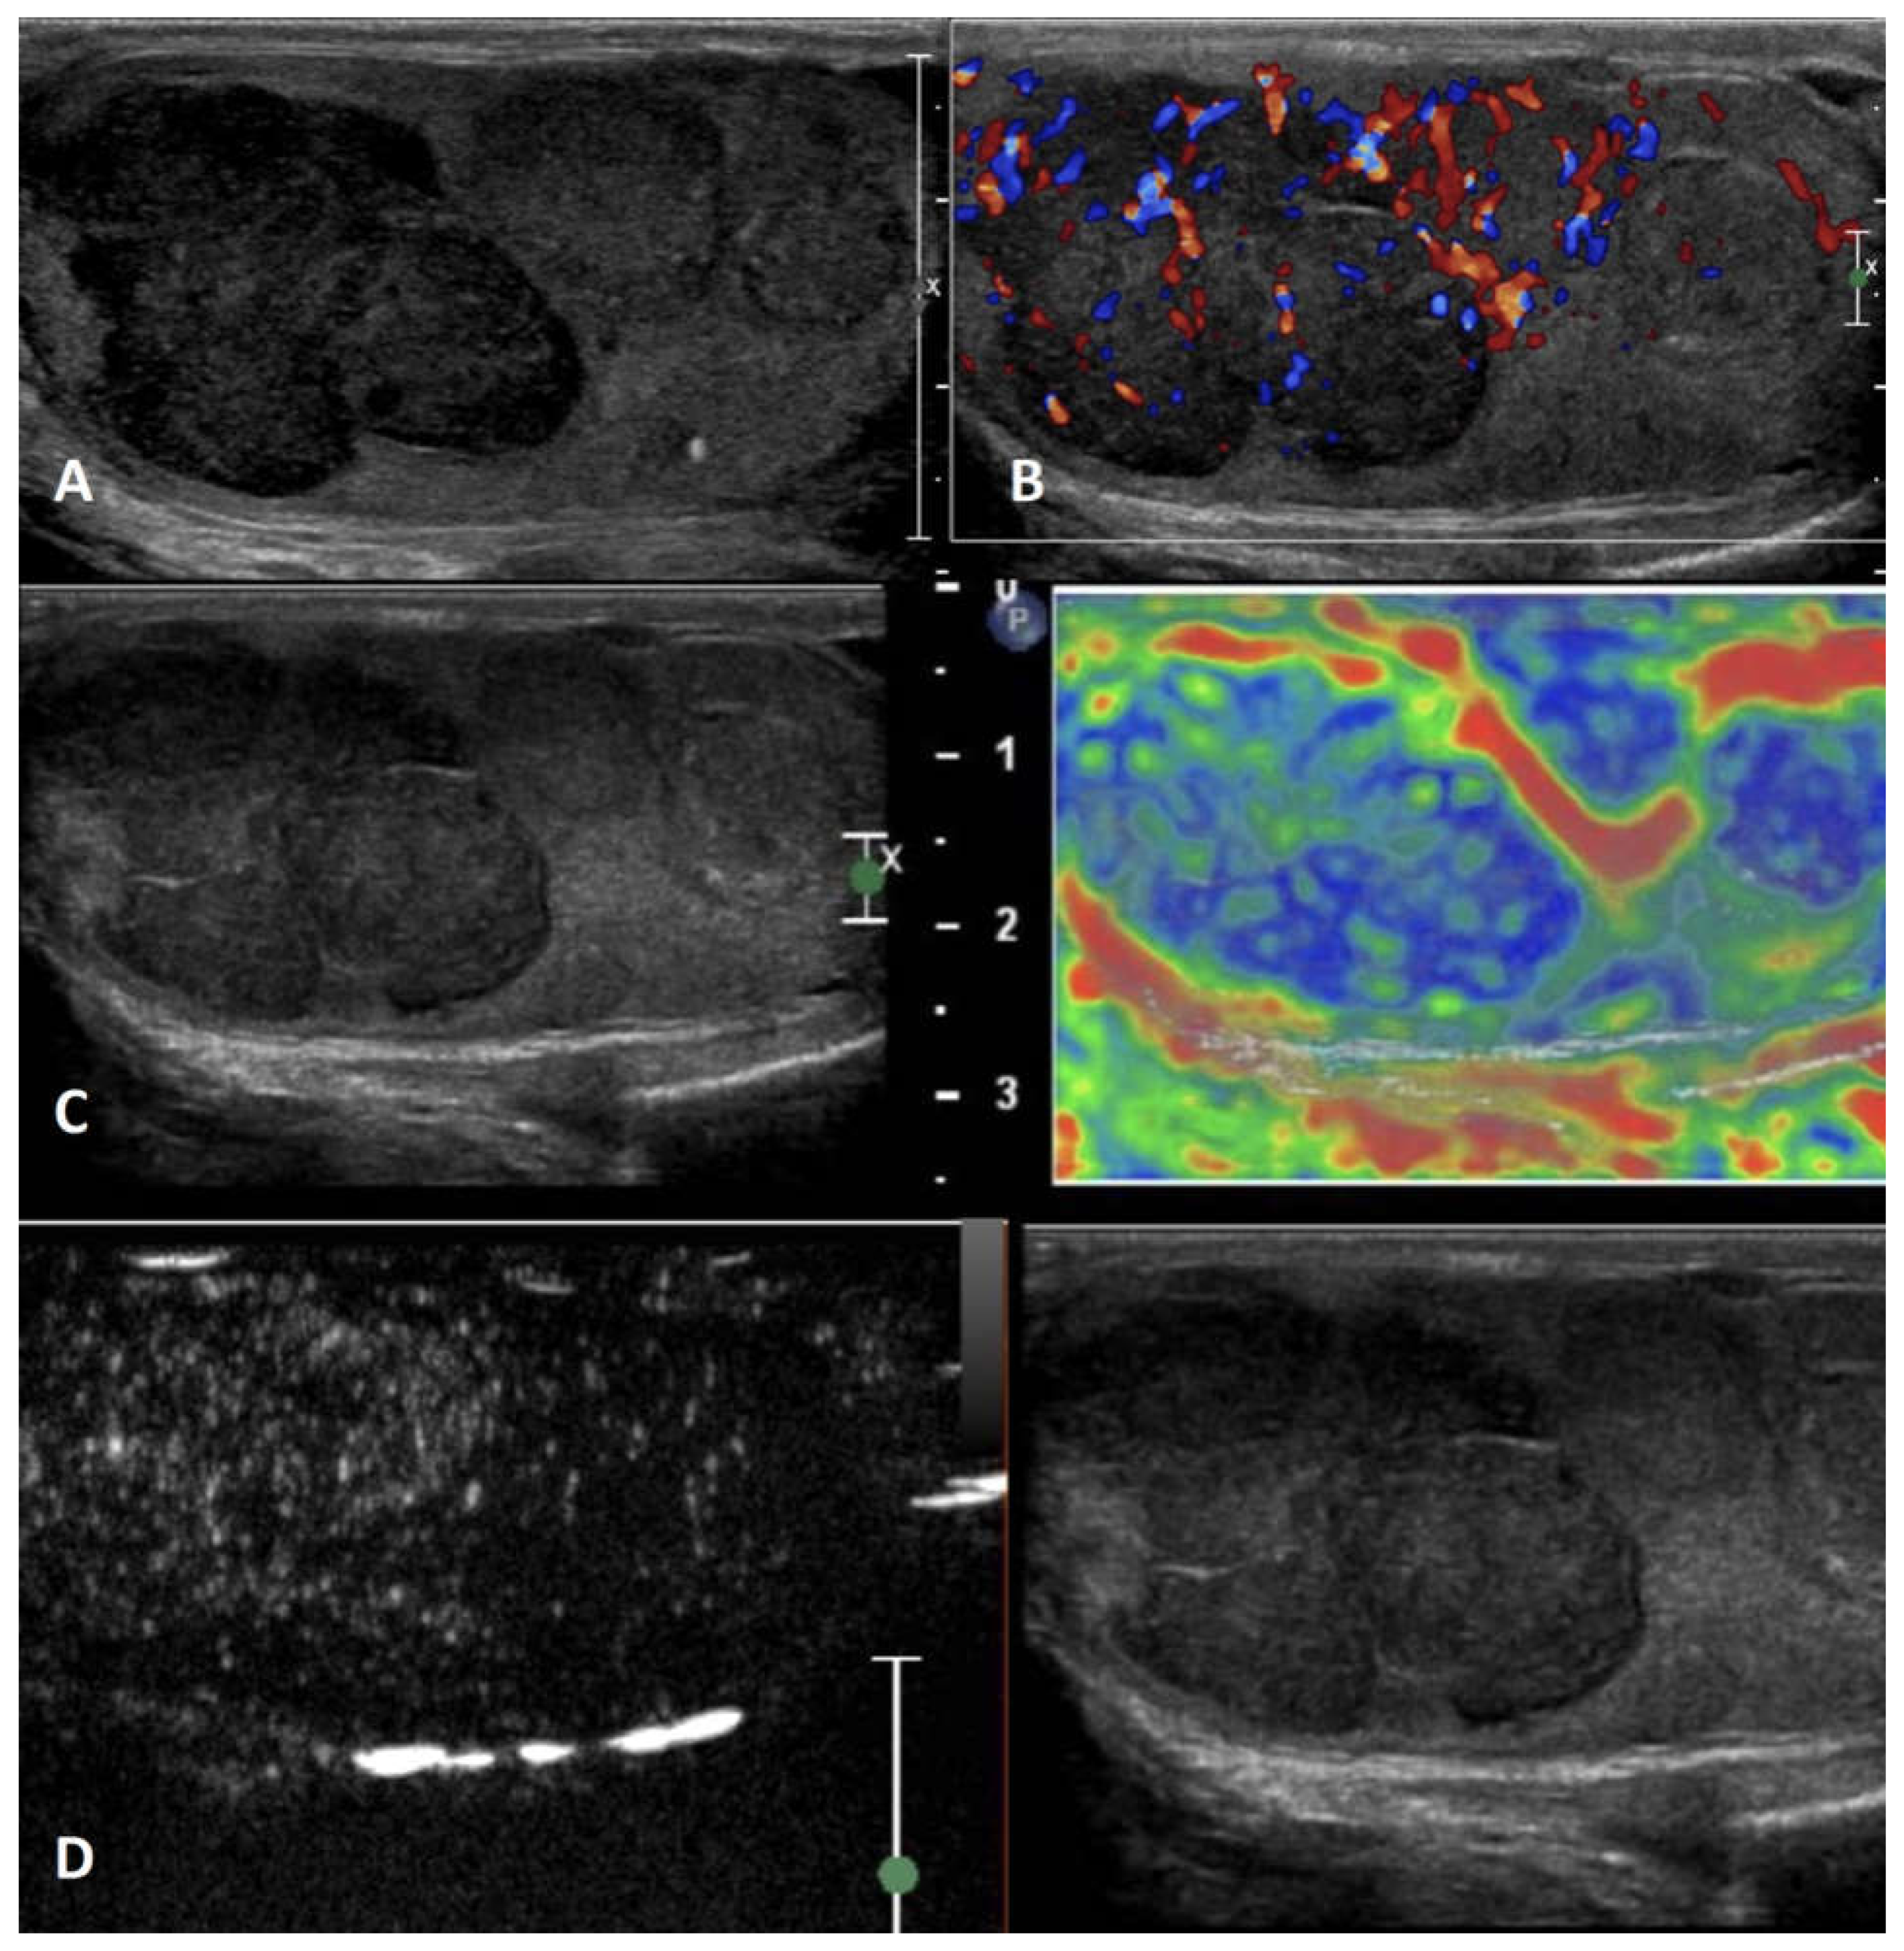

6.4.1. Lymphoma

6.4.2. Primary testicular leukemia

| Neoplastic intratesticular lesions | ||||||

| Clinical presentation | Serum tumor markers | GSUS | CDUS | CEUS | SE | |

| Lymphoma | testicular swelling, pain, and specific lymphoma symptoms; affects men older than 50 years, palpable firm testicular mass |

Negative | Hypoechoic lesions with diffuse infiltration or multifocal hypoechoic lesions of various size | Hypervascularized with linear non-branching pattern | Hyperenhanced | Hard lesions with low/absent elastic strain |

| Leukaemia | More frequent in children and young patients; it can be asymptomatic | Negative | Infiltrating pattern with irregular hypoechoic longitudinal striae/ focal pattern with irregular hypoechoic nodules | Hypervascularized | Inhomogeneously hyperenhanced |

Hard lesions with low/absent elastic strain |